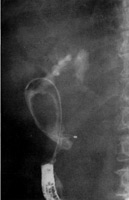

Η MRCP απεικονίζει με αρκετή ακρίβεια το χοληφόρο και παγκρεατικό δένδρο και

είναι εξέταση που προτιμάται σε παιδιά. Η ERCP είναι επεμβατική μέθοδος, προϋποθέτει

μεγάλη εμπειρία, ιδίως στην εφαρμογή της στα παιδιά και έχει αυξημένες πιθανότητες

επιπλοκών (αιμορραγίας ή παγκρεατίτιδας) (εικόνα 7).

EIKONA 7.

Πάγκρεας. MRCP. Κύστεις χοληδόχου και παγκρεατικού πόρου.

Πάγκρεας MRCP. Διάταση παγκρεατικού πόρου.

Πάγκρεας ERCP